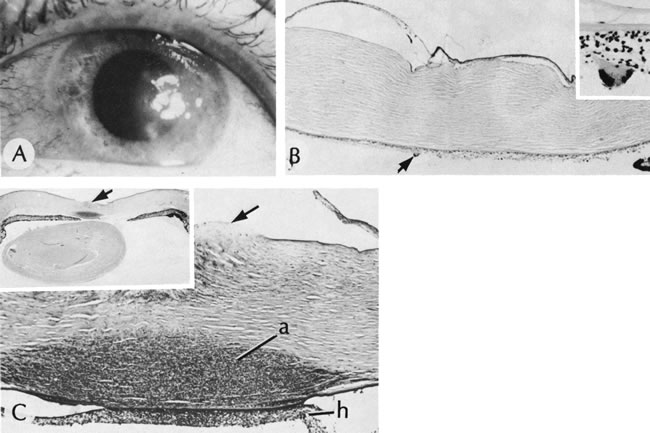

Viral Corneal Ulcers

Herpes simplex is the most common cause of viral central corneal ulcers in the United States.120 The initial clinical sign may be a cutaneous vesicular rash (Fig. 17) or a corneal epithelial dendrite (Fig. 18). The infection progresses through corneal stromal inflammation (metaherpetic phase) to culminate in central ulceration. The initial epithelial defect is caused by replication of herpes simplex virions in the epithelial cells; the cytopathologic effect of the infection leads to epithelial cell death (rose bengal–positive) and ulceration. The infection is self-limited to an 8- to 10-day course unless shortened by debridement or antiviral therapy. The recurrence rate of initial dendritic infection by herpes simplex (25%) is not influenced by the type of treatment used. Most of the significant complications, such as corneal ulceration (Fig. 19), of herpetic keratitis are related to its tendency to initiate a delayed hypersensitivity type IV reaction, rather than the result of direct infection of the stroma.

By light microscopy, eosinophilic intranuclear inclusions are characteristic of herpes simplex viral infections and represent the result of viral replication (Cowdri type A inclusions).121 Hypersensitivity type IV reactions in the stroma are characterized by lymphocytic and plasmacytic infiltrates. Intranuclear inclusions are relatively rare and are not found in most specimens. Viral particles occasionally can be found in multinucleated giant cells or within the stroma, especially in keratocytes (Figs. 20 and 21).

Fig. 21. Herpes simplex. A. Clinical appearance of bullous keratopathy. B. Chronic condition shows development of bullous keratopathy. The anterior chamber inflammatory reaction contains multinucleated inflammatory giant cells (arrow), shown under high magnification in inset. C. Ulcerated bullous keratopathy (arrows). A corneal abscess (a) and hypopyon (h) are present. Note (inset) the subluxation of the lens to left, caused by the loss of zonula-lens attachments on the right, resulting in a “blunted” appearance of the right side of the lens. (Courtesy of SEI Photoarchives.)